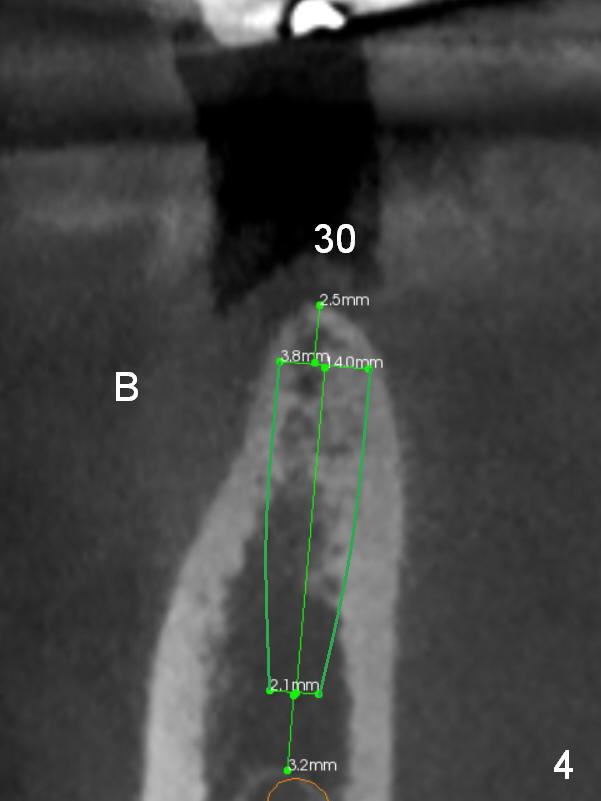

The narrow ridge at #30 will be split with wheel saw; osteotomy will be finished using bone expanders (Fig.4).